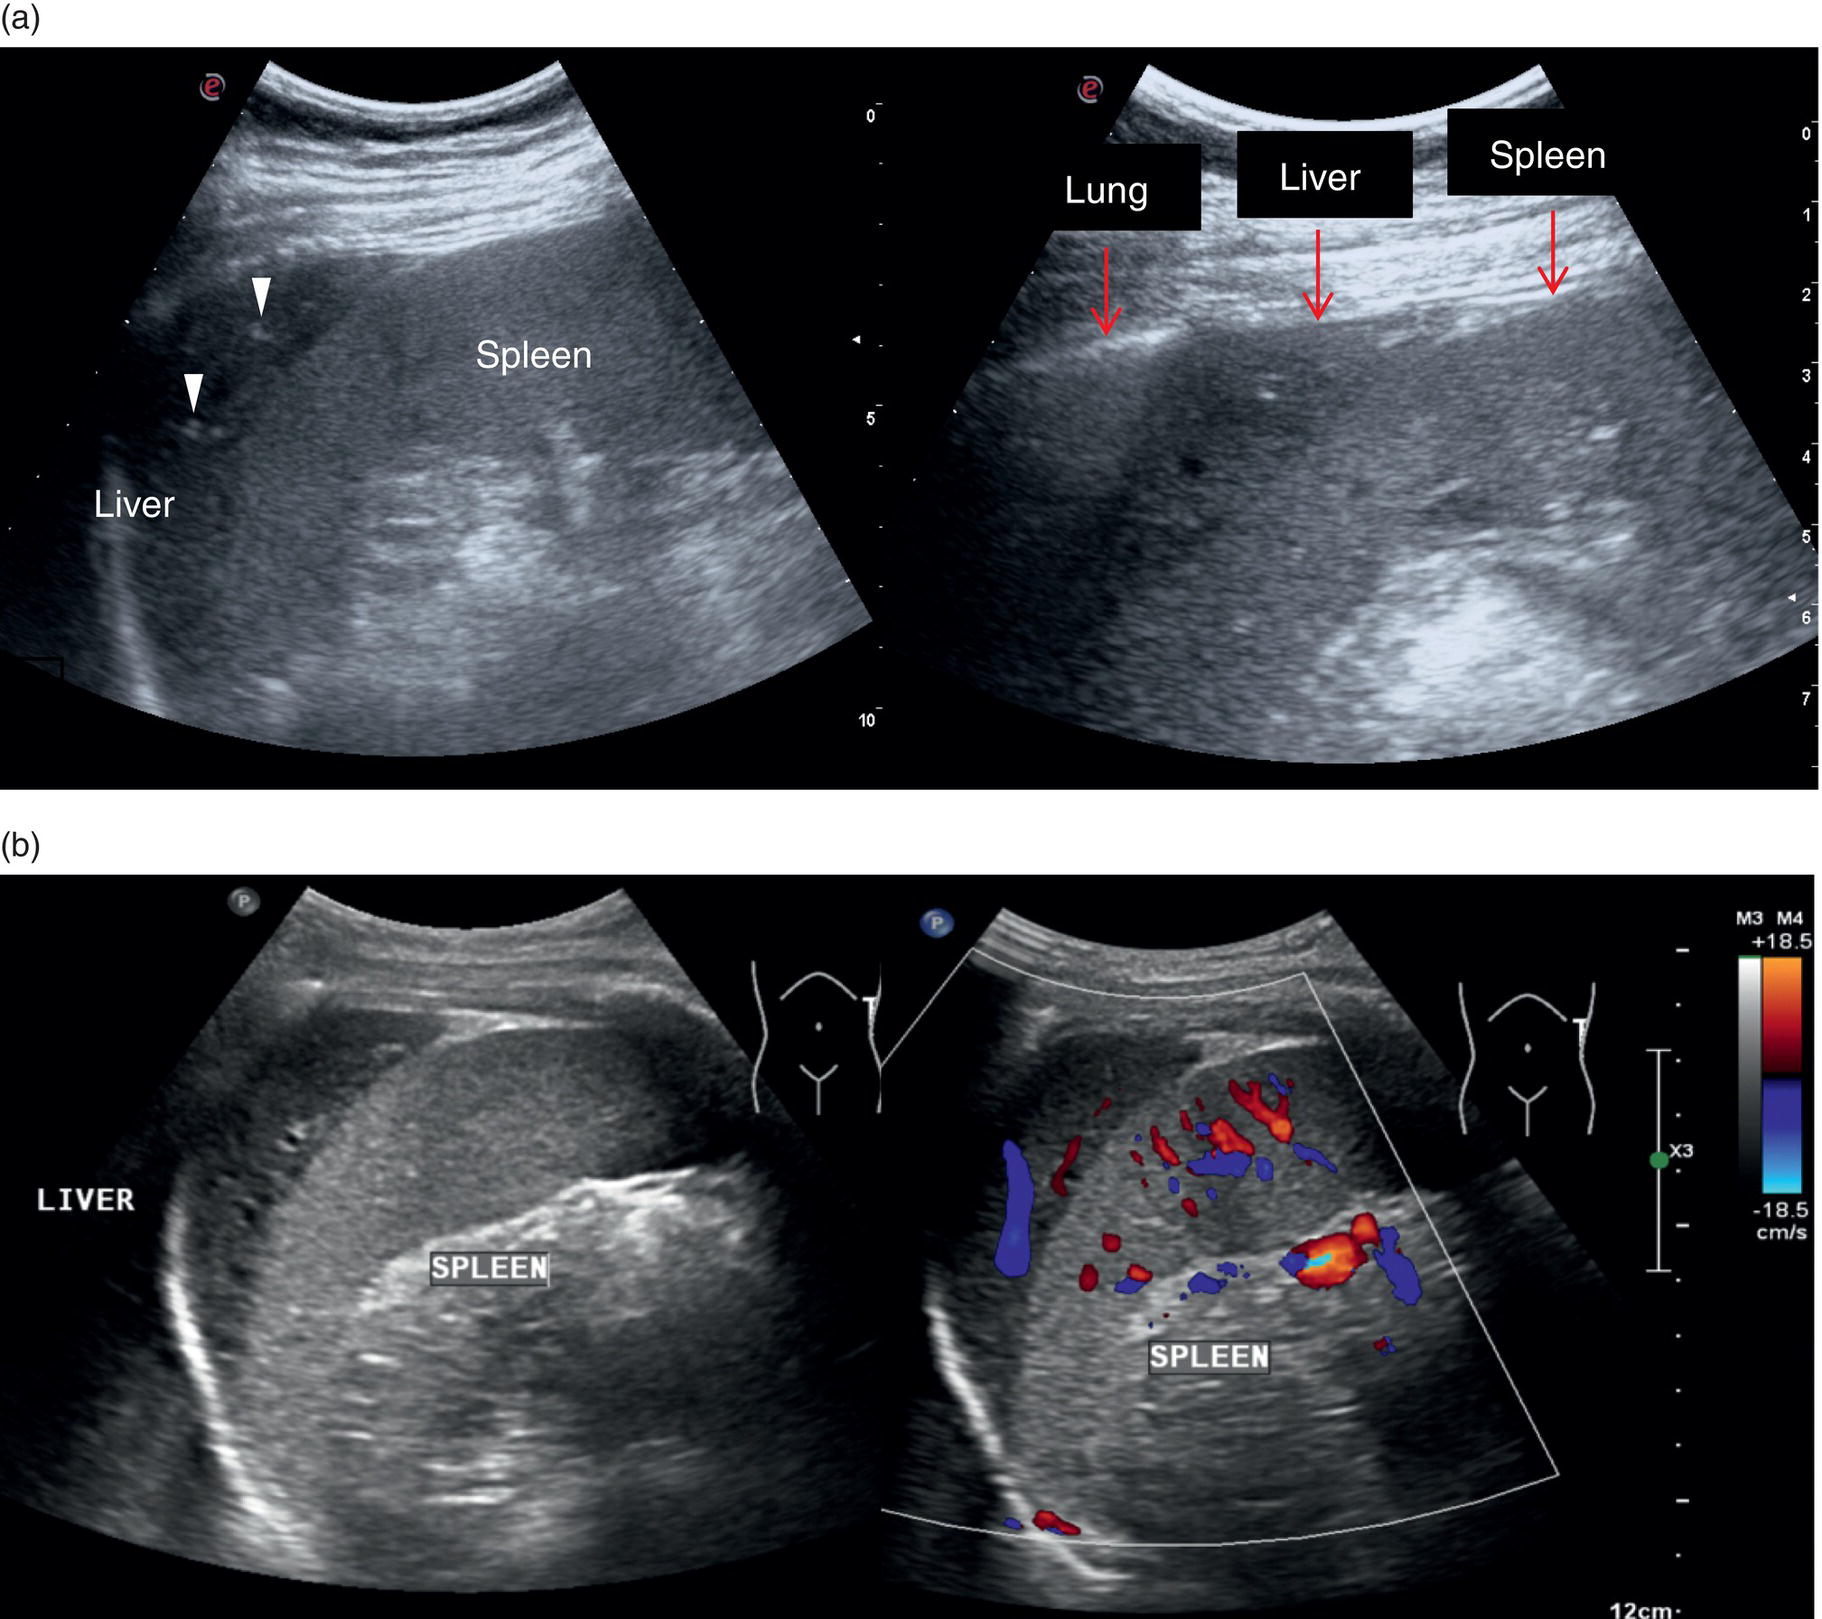

The Spleen

The spleen is a very important organ in liver disease, since it is linked anatomically and physiologically to the liver through the portal venous system. Its increase in size is described as one of the hallmarks of significant portal hypertension in cirrhosis (see Chapter 8), although extrahepatic causes of splenomegaly should always be borne in mind. Therefore, when performing a liver ultrasound scan, the size of the spleen must always be described, highlighting both longitudinal and anteroposterior diameters (respective cut‐offs ≤13 cm and ≤4 cm). However, splenic parenchymal evaluation is also very important in addition to the splenic size, where textural differences can be seen with different pathological conditions ranging from infectious diseases, haematological and immune/inflammatory‐related pathologies as well as congenital and acquired vascular malformations. Moreover, splenic parenchyma can also be the site of benign and primary or secondary malignancies manifesting as discrete focal lesions. Of note, accessory spleens (splenunculi) are relatively common (Figure 3.39). These are typically rounded or ovoid small lesions with similar splenic echotexture and vascularity. They are a result of the incomplete fusion of splenic tissue into a single organ during its embryonal development and thus can occur anywhere along the splenic bed. Occasionally, these can be difficult to distinguish from peritoneal or renal lesions and thus may require contrast ultrasound or further imaging for confirmation.The spleen is assessed intercostally through the left lateral intercostal spaces with the patient lying supine. Keep in mind that in some cases the spleen is more posterior and difficult to visualise entirely (Figure 3.39). In case of splenomegaly, the spleen can be assessed with a longitudinal subcostal scan; alternatively, in case of a normal‐sized spleen the intercostal approach remains the best option. Imaging may be improved sometimes by turning the patient right side down, although sometimes bowel loops and the lung might interfere, leading to suboptimal imaging.

Liver anatomical variants might be related to the shape, size, and vasculature, as well as the GB and biliary tree. Parenchymal variants include diaphragmatic slips, sliver of liver, Riedel’s lobe, and papillary process of the caudate lobe [5]. Diaphragmatic slips represent incomplete accessory fissures at the site of the diaphragmatic liver surface due to invagination of the diaphragm (Figure 3.16). A sliver of the liver refers to an anatomical variant where the left liver lobe extends to the left hypochondrium, wrapping around part of the spleen (Figure 3.17). Another common variant is a Riedel’s lobe, represented by a downward tongue‐like projection of the lower anterior edge of the right liver lobe (segment VI), sometimes so pronounced as to extend along the right paracolic space up to the iliac fossa (Figure 3.18) [6]. The papillary process is an anterior and medial extension of the caudate lobe, which might resemble a lymph node or mass next to the pancreatic head or IVC (Figure 3.19).